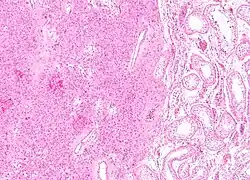

| Histopathology of a Leydig cell tumor, high magnification, H&E stain, showing typical features.[1] | |

A conclusive diagnosis is made via histology, as part of a pathology report made during or after surgery. Reinke crystals are classically found in these tumours and help confirm the diagnosis, although they are seen in less than half of all Leydig cell tumours. Immunohistochemical markers of Leydig cell tumours include inhibin-alpha, calretinin, and melan-A.[9]